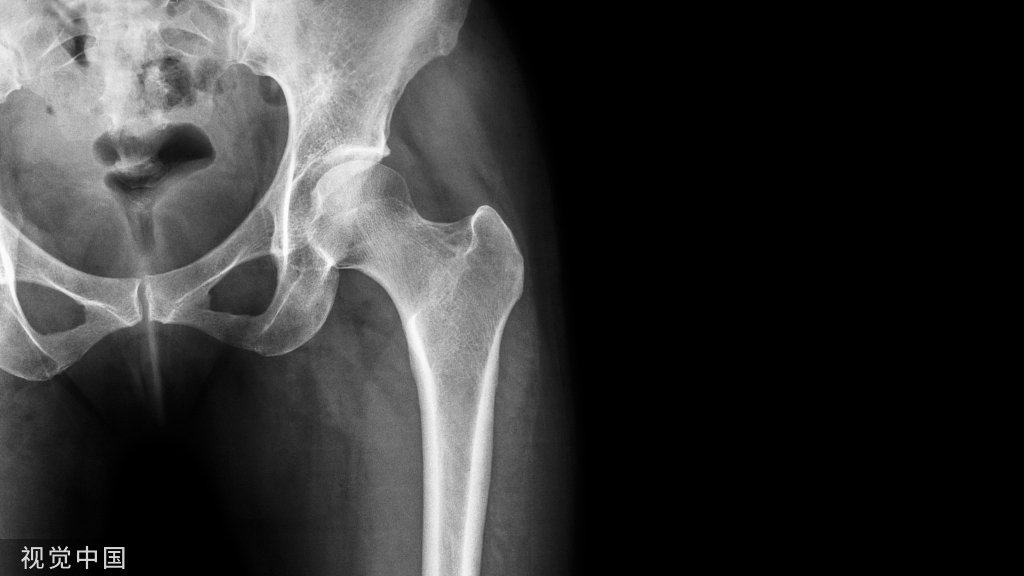

59岁女性行C3-7ACDF,处理C5/6时突然喷涌鲜红血液约500ml,用强生的Nu-Knit止血材料填塞止血后停止后续手术步骤,关闭切口。

术前颈椎MRI其实已提示C5/6间盘左侧有血管流空信号,但和椎间盘信号混一起,容易一眼过,被忽略。

即刻介入造影显示C5/6左侧椎动脉环袢状走行异常和假性动脉瘤。

术后第4天,CTA示疝入椎间盘层面的左侧椎动脉,假性动脉瘤增大,遂行介入封堵。一个月后再行ACDF手术。此后患者病情平稳,恢复良好。

ACDF的椎动脉损伤率为0.06%,ACCF为0.5%。伴随的神经系统并发症从C5根损伤到小脑梗死、瘫痪,发生率约50%。

钩椎关节的钩状突起是一面安全墙,椎动脉紧贴旁边大约有1mm空隙,一般显露到钩突时就要小心了 。

随着个人年龄增长,钩状突起开始变秃,失去其特征性外观,很容易显露偏外损伤血管。

如果术中椎动脉损伤,止血第一。技术硬可以直接修补。但大多数医生做不到,还是压塞、结扎最常用也最有用。

损伤主要有三个风险:血肿、假性动脉瘤和动静脉瘘。并发症有血栓栓塞、脑缺血、气道损伤、吞咽困难和大出血。血管造影随访是关键。

术前通过CT或核磁T2相仔细评估,观察有无椎动脉异常。怀疑有问题就做CTA、MRA。目前AO spine手册已将椎动脉CTA作为颈椎术前必查项目,以排除椎动脉畸形造成的潜在医源性损伤。